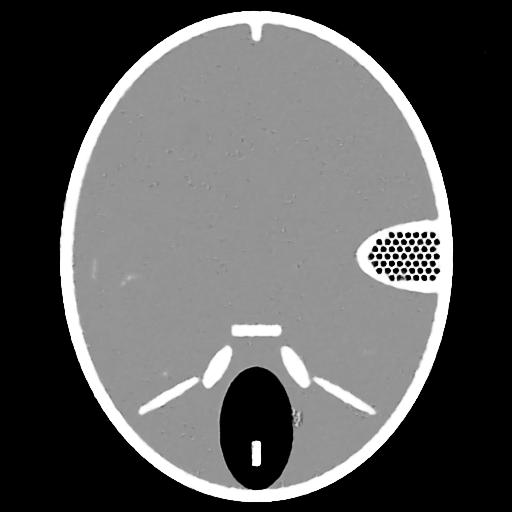

Then, we evaluate the performance of the SDIP framework under conditions of both few-view and limited-angle, in comparison to the original DIP method and the conventional IR method. To further verify the effectiveness of the SDIP, an additional set of experiments was conducted (termed SDIP-GT). In the SDIP-GT, it is presumed that the steering algorithm is privy to the ground truth image. Consequently, line 6 of Algorithm 1 is modified to , where represents the ground truth image. If the proposed self-reinforcement mechanism can enhance the algorithm’s performance effectively, then SDIP-GT, which utilizes ground truth images to steer the algorithm, should achieve superior accuracy. The experiment results are shown in Fig.8 and Fig.9, where SDIP-GT maintains the highest performance and is nearly immune to the decreased number of measurements. SDIP outperforms the original DIP and the IR method. The reconstruction results of Forbild phantom [33] under few-view, limited-angle, and complete-view conditions are illustrated in Fig.10, it is evident that the conventional IR method suffers from severe artifacts. The original DIP approach substantially mitigates these artifacts, achieving notable improvements. The proposed SDIP framework achieves the best reconstruction results which are nearly artifact-free.